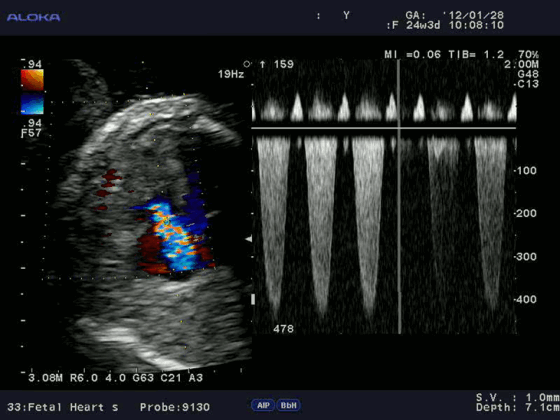

Допплерэхокардиография позволяет измерить все вышеперечисленные параметры, которые очень важны при оценке детской сердечной патологии (врожденные пороки) без использования инвазивной процедуры — катетеризации сердца. Помимо этого, назначение эхокардиографии с допплеровским анализом ребенку не несет никакой угрозы по сравнению с компьютерной томографией, где используется рентгеновское излучение.

Цветовой допплер (Color Doppler). Цветовой допплер - аналог импульсного допплера, где направление и скорость кровотока картируется различным цветом. Так кровоток к датчику принято картировать красным цветом, от датчика - синим цветом. Турбулентный кровоток картируется сине-зелено-желтым цветом.

Цветовой M-модальный допплер (Color M-mode). Сопоставление M-модального режима и цветового допплера при проведении курсора через ту или иную плоскость, позволяет разобраться в фазами сердечного цикла и патологическим кровотоком.